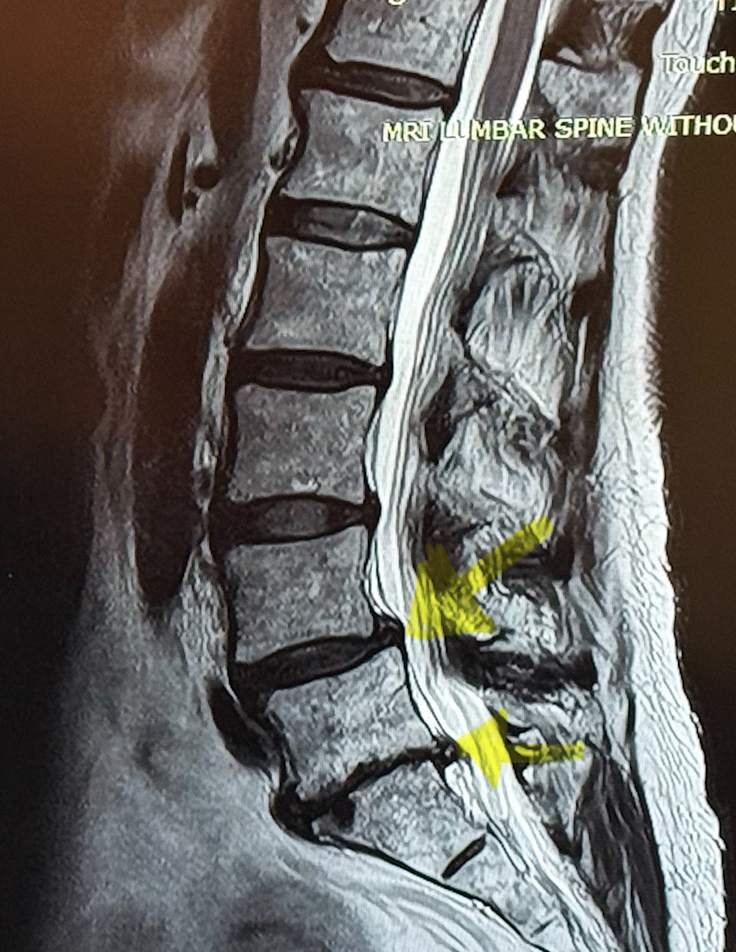

1. Spondylolisthesis (disks out of alignment) on 2 disks. (See Photo 1). Notice the yellow arrows and the disk that has slid to the side.

Photo 1